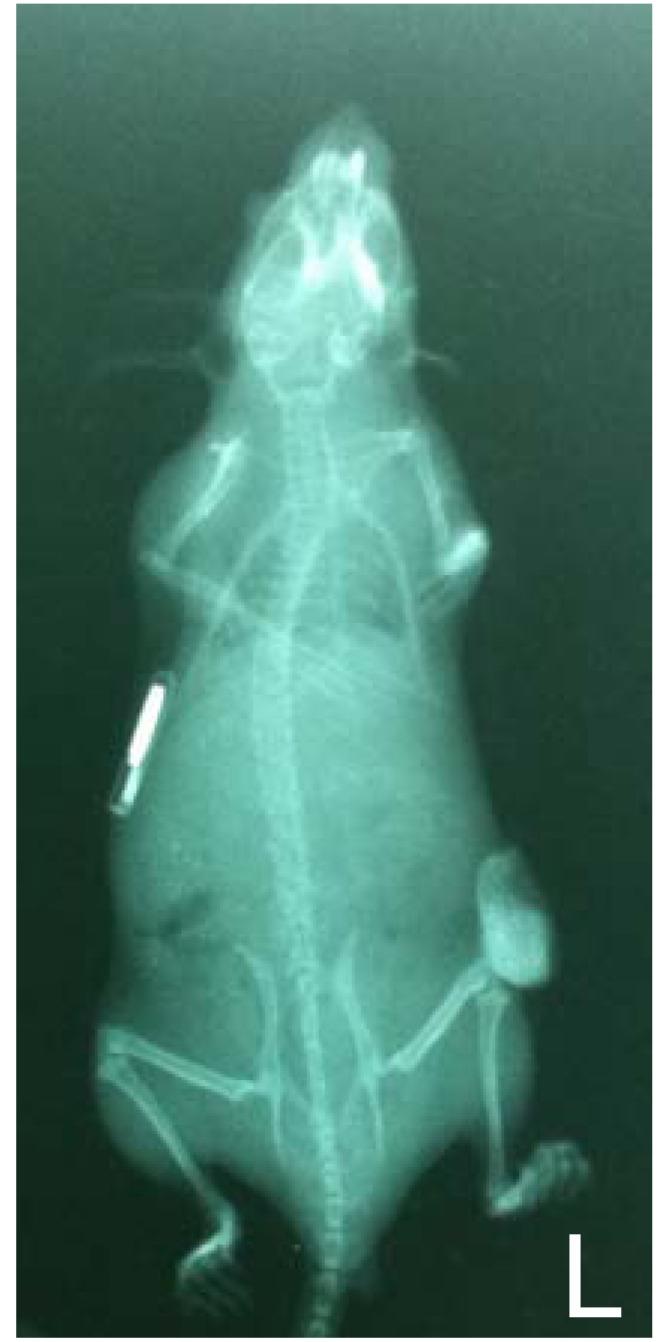

Mouse models of multiple myeloma (MM) are basic tools for translational research and play a fundamental role in the development of new therapeutics against plasma cell malignancies. All available models, including transplantable murine tumors in syngenic mice, xenografts of established human cell lines in immunocompromised mice and transgenic models that mirror specific steps of MM pathogenesis, have demonstrated some weaknesses in predicting clinical results, particularly for new drugs targeting the human bone marrow microenvironment (huBMM). The recent interest to models recapitulating the in vivo growth of primary MM cells in a human (SCID-hu) or humanized (SCID-synth-hu) host recipient has provided powerful platforms for the investigation of new compounds targeting MM and/or its huBMM. Here, we review and discuss strengths and weaknesses of the key in vivo models that are currently utilized in the MM preclinical investigation.

多发性骨髓瘤 (MM) 的小鼠模型是转化研究的基本工具,对开发针对浆细胞恶性肿瘤的新疗法起着至关重要的作用。所有现有的模型,包括同种异体小鼠中的可移植鼠肿瘤、免疫缺陷小鼠中的已建立人细胞系的异种移植物以及模拟 MM 发病机制特定步骤的转基因模型,在预测临床结果方面都存在一些局限性,特别是对于针对人骨髓微环境 (huBMM) 的新药。最近,人们对能够在人 (SCID-hu) 或人源化 (SCID-synth-hu) 宿主受体中重现原发性 MM 细胞体内生长的模型产生了兴趣,为针对 MM 及其 huBMM 的新化合物的研究提供了强大的平台。在这里,我们回顾和讨论了目前在 MM 临床前研究中使用的关键体内模型的优缺点。